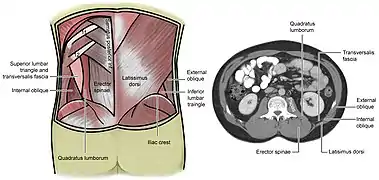

| The superior and inferior lumbar triangles with a cross section at the level of the superior lumbar triangle | |

Grynfeltt–Lesshaft hernia is a herniation of abdominal contents through the back, specifically through the superior lumbar triangle, which is defined by the quadratus lumborum muscle, twelfth rib, and internal oblique muscle.